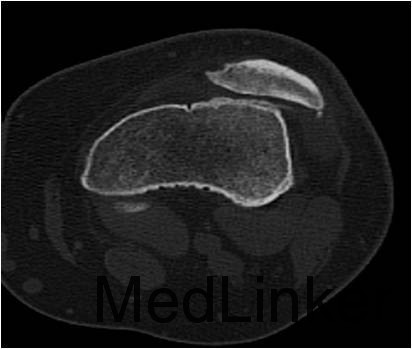

患者男,28岁,因”摔伤致左膝关节髌骨脱位7年余“入院。患者7年前无明显诱因反复出现髌骨脱位,近1个月发生3次脱位。

查体:左膝关节麦氏征(+),浮髌征(+),髌骨加压研磨试验(+),髌骨恐惧试验(±),右膝关节及双上肢未见明显异常。CT及MRI提示:1.左膝关节复发性髌骨脱位;2.左膝关节髌股关节炎。

诊断:1.左膝关节复发性髌骨脱位;2.左膝关节髌股关节炎。拟行左膝关节镜检,关节腔清理,骨赘切除和软骨面修整术。